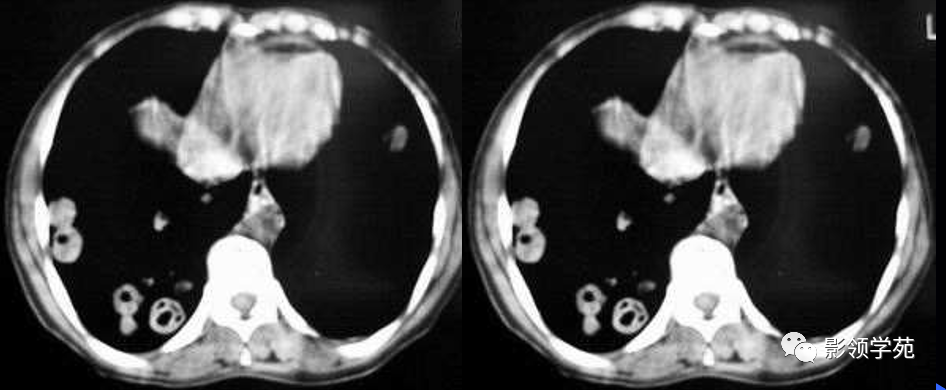

1. 血行性转移 :

多发或单发结节,大小不一,边缘较清楚。少数结节伴出血时出现晕轮征,即有略高密度影像环绕结节,使病变边缘模糊。病变有钙化常见于骨肉瘤或软骨肉瘤转移。转移瘤亦可表现为空洞。两肺多发的小结节影具有随机分布的特点,HRCT显示结节位于小叶中心、小叶间隔、支气管血管束及胸膜,结节大小不均匀。

肺转移瘤。肺窗像(A)示双肺野可见大小不等的圆形高密度结节影,纵隔增宽;纵隔窗像(B)示肺内肿块呈实性,纵隔满布大小不等的肿大淋巴结

CT诊断:甲状腺癌双肺多发转移